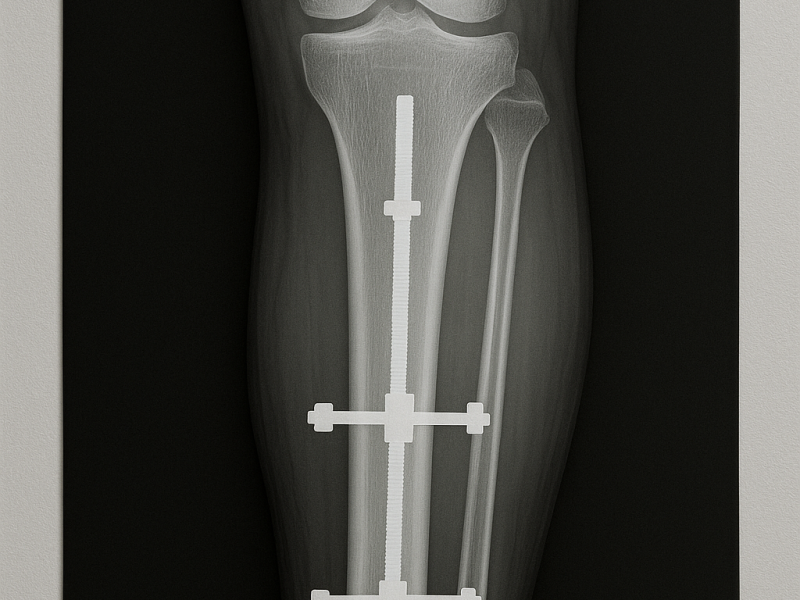

La traumatologia si occupa del trattamento delle lesioni dell’apparato muscolo-scheletrico causate da traumi, incidenti o attività sportive.

Fratture, distorsioni e lesioni dei tessuti molli richiedono una diagnosi rapida e un trattamento adeguato per garantire un recupero completo.

Gestione delle Lesioni

Il trattamento viene scelto in base al tipo e alla gravità del trauma e può includere:

Immobilizzazione

Terapie conservative

Interventi chirurgici di ricostruzione

Obiettivo del Trattamento

Ripristinare la funzionalità dell’articolazione

Ridurre il dolore

Prevenire complicazioni future

Il paziente viene seguito durante tutto il percorso di guarigione e riabilitazione.